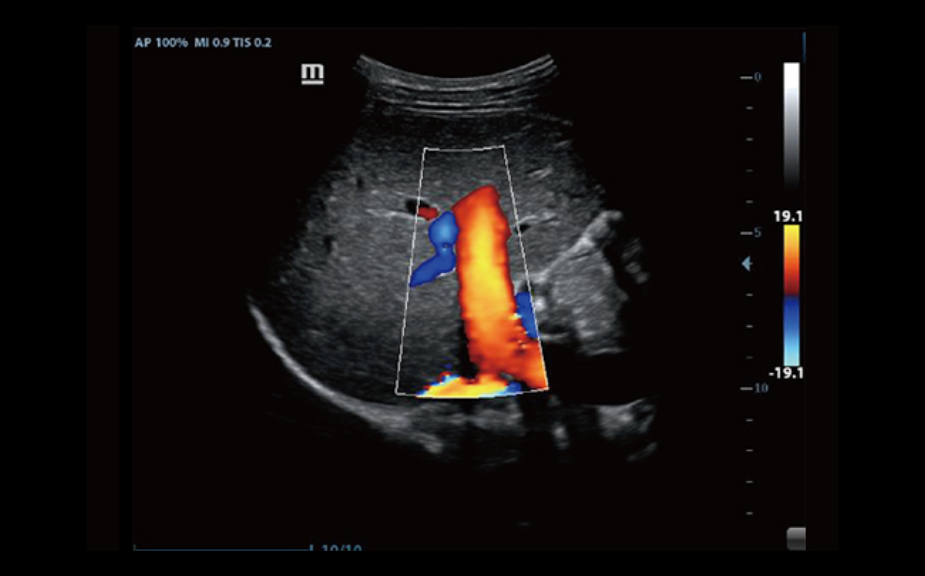

iScape?

Pozwala na uzyskanie pe?nego i poszerzonego podgl?du struktury anatomicznej poprzez zastosowanie obrazowania panoramicznego, w po??czeniu ze wskazaniem pr?dko?ci i mo?liwo?ci? skanowania w prz├│d/w ty?. Dzi?ki temu skanowanie jest znacznie ?atwiejsze, p?ynniejsze i bardziej kontrolowane.

ExFOV

Pozwala odkry? wi?cej informacji diagnostycznych poprzez poszerzenie obrazu i mo?liwo?? obrazowania wi?kszych struktur anatomicznych na wszystkich sondach convex i liniowych.